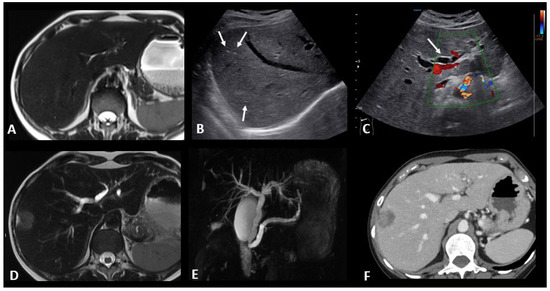

2.4.4. Ir-Cholangitis

- Gosangi, B.; McIntosh, L.; Keraliya, A.; Irugu, D.V.K.; Baheti, A.; Khandelwal, A.; Thomas, R.; Braschi-Amirfarzan, M. Imaging features of toxicities associated with immune checkpoint inhibitors. Eur. J. Radiol. Open 2022, 9, 100434. [Google Scholar] [CrossRef] [PubMed]

- Pi, B.; Wang, J.; Tong, Y.; Yang, Q.; Lv, F.; Yu, Y. Immune-related cholangitis induced by immune checkpoint inhibitors: A systematic review of clinical features and management. Eur. J. Gastroenterol. Hepatol. 2021, 33 (Suppl. S1), e858–e867. [Google Scholar] [CrossRef]